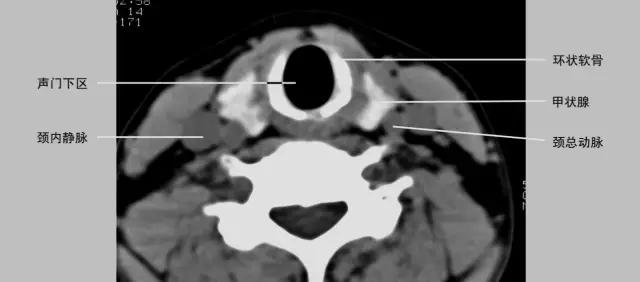

正常喉部CT

- 声门下区为声带下至环状软骨下缘以上的喉腔,正常气道与环状软骨间粘膜厚度不超过1mm。

2、CT、MRI检查

喉软骨:软骨骨化及髓腔形成的程度。

1、年轻人软骨未骨化,T1及T2WI等信号,CT等密度,与其它软组织较难区分。

2、30岁以上成年人T1WI中央高信号代表脂肪及黄骨髓生成。年老时骨化变为皮质骨,信号减低。CT为高密度。

3、会厌软骨由弹性软骨组成,T1WI略低于肌肉,T2WI略高于肌肉。CT呈等密度,少有钙化。